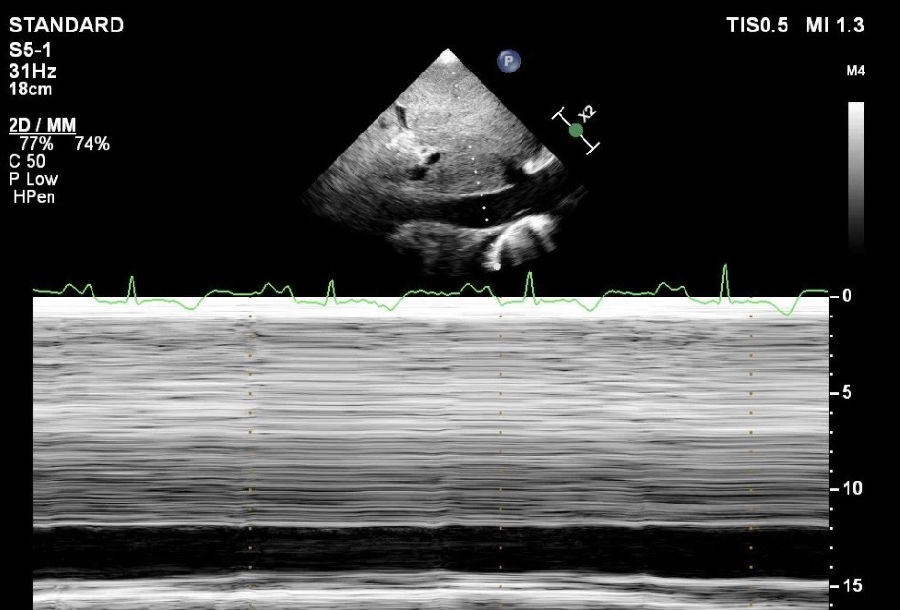

下腔静脉内径增宽,吸气塌陷率<50%。

超声诊断:阳性所见考虑:缩窄性心包炎。

2. 二维超声:典型的声像图可见心包回声增强,双心房增大,心室减小,房室沟处常有纤维带或钙化,室间隔异常运动(舒张期向左心室内摆动并即刻弹向右心室)。除双心房扩大以外,心包增厚是诊断的重要依据。经食管超声观察心包增厚明显优于经胸超声。此外缩窄性心包炎在二维超声上还可显示:下腔静脉扩张,吸气时塌陷率<50%(提示右心房压力升高)。